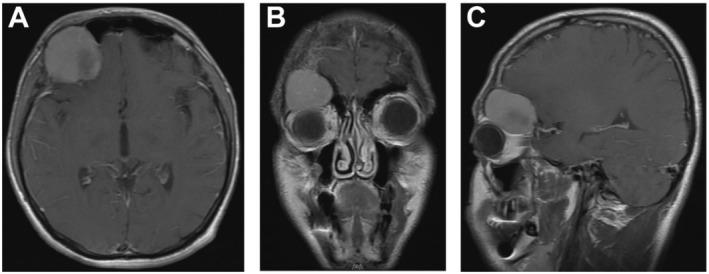

Osteoblastoma is an uncommon benign bone tumor rarely involving the craniofacial skeleton. Manifestations in the fronto-orbital region are exceptionally rare. A 19-year-old man presented with persistent headache, nausea, vomiting, right eye pain, and longstanding right exophthalmos. Imaging revealed a heterogeneous enhancing lesion located in the right anterior cranial fossa-orbital apex junction causing pressure on the orbital roof. Differential diagnoses included fibrous dysplasia and meningioma. The tumor was resected via frontal craniotomy. Definitive diagnosis of osteoblastoma was achieved postoperatively through histopathological examination and IHC studies. Craniofacial osteoblastomas, especially in the fronto-orbital region, are exceptionally rare and may present radiological features similar to other bone pathologies. Accurate diagnosis hinges on histopathological evaluation. A multidisciplinary approach is pivotal for successful diagnosis and treatment of such challenging cases.

摘要

骨母细胞瘤是一种罕见的良性骨肿瘤,很少累及颅面骨骼。额眶区域的表现极为罕见。一名19岁男性出现持续性头痛、恶心、呕吐、右眼疼痛和长期的右眼球突出。影像学检查显示一个位于右前颅窝-眶尖交界处的不均匀强化病变,对眶顶产生压迫。鉴别诊断包括骨纤维发育不良和脑膜瘤。通过额部开颅手术切除肿瘤。术后通过组织病理学检查和免疫组化研究确诊为骨母细胞瘤。颅面骨母细胞瘤,尤其是在额眶区域,极为罕见,可能呈现与其他骨病变相似的放射学特征。准确的诊断取决于组织病理学评估。多学科方法对于成功诊断和治疗此类具有挑战性的病例至关重要。